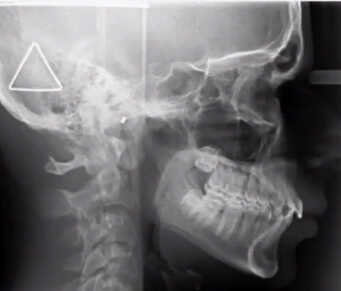

Sleep Apnea In Children Example

While obstructive sleep apnea is commonly associated with adults, it is important to recognize that children can also be affected by this condition. Pediatric obstructive sleep apnea refers to a sleep disorder in which a child’s breathing is partially or completely obstructed during sleep, leading to disrupted breathing patterns and inadequate rest. The underlying cause of this condition is often the narrowing or blockage of the upper airway during sleep.

Enlarged tonsils or adenoids are frequent culprits of obstructive sleep apnea in children. However, other factors, such as genetic predisposition, nasal allergies, Down syndrome or cerebral palsy, may also increase the risk of pediatric sleep apnea.